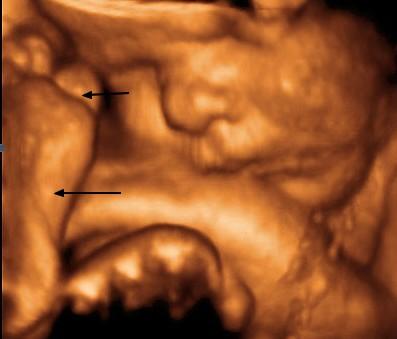

Snímek jasně demonstruje, že v prostoru vymezeném plodovými obaly začíná být plodu poněkud těsno. V blízkosti obličeje jsou zachyceny jak horní, tak dolní končetina. Na chodidle nožičky (dolní šipka) je dobře patrný mohutnější paleček (horní šipka) a štíhlejší prsty.